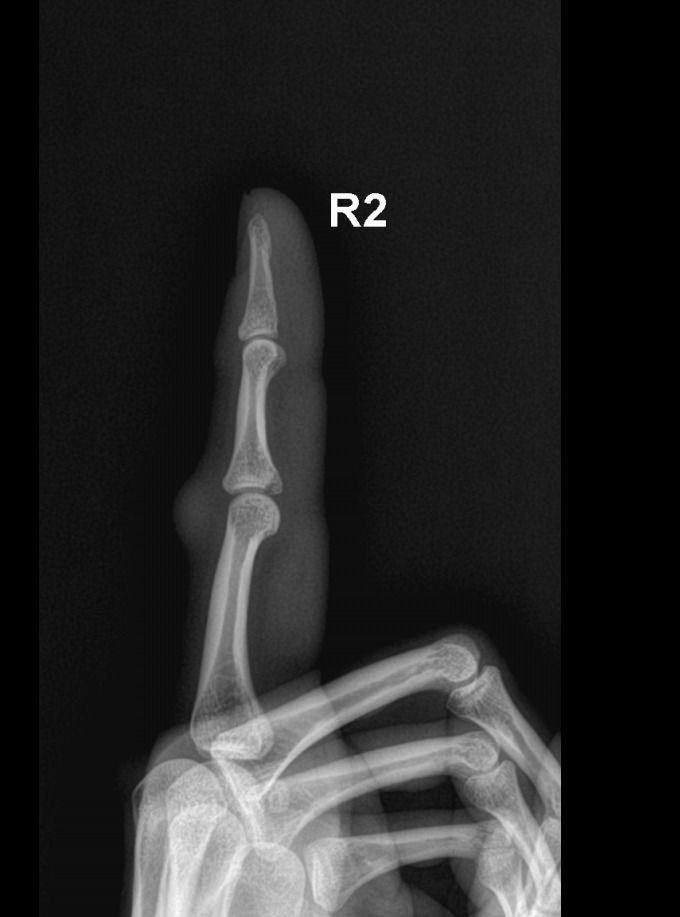

Как выглядит снимок перелома внутренней стороны второй фаланги соударением? Перелом второго пальца правой руки

Рентгенограмма кисти. Как выглядит снимок перелома внутренней стороны второй фаланги соударением? Перелом второго пальца правой руки